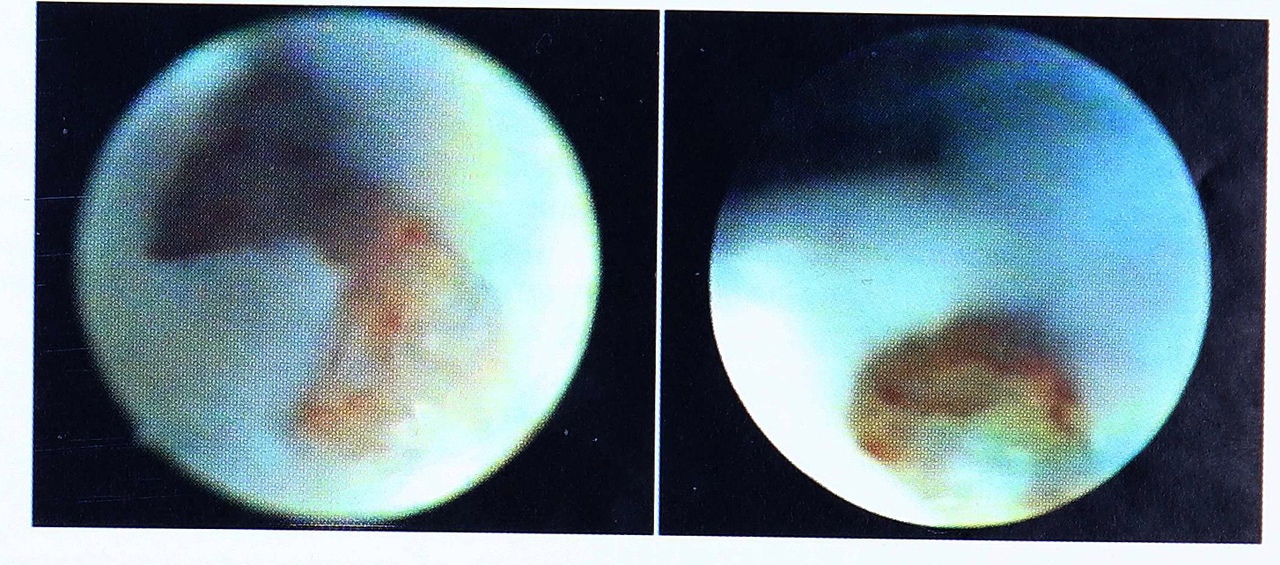

После проведенной динамической демпферной разгрузки правого тазобедренного сустава выполнена артроскопия. Под наркозом из переднего доступа в полость сустава после предварительного наполнения его стерильным раствором новокаина (0,5% в 20 мл физиологического раствора) через инъекционную иглу введено 5 мл 60% урографина с 5 мл 0,5% новокаина. Выполнена контрастная артрография в переднезадней проекции: контрастное вещество проникает в полость сустава, конец иглы прослеживается в суставной щели. Тупым троакаром произведена перфорация капсулы сустава. Получено 10 мл синовиальной жидкости (прозрачная, обычного цвета). В полость сустава в передненаружный квадрант введены промывная и оптическая системы. Из переднебокового доступа произведена ревизия сустава, показавшая следующее (рис. 3): вертлужная впадина выполнена грубоволокнистой тканью, жировая подушка не визуализируется, имеется полный отрыв круглой связки в месте прикрепления к головке бедренной кости, сама головка неправильной формы, с нарушенной сферичностью, диффузными выбуханиями на поверхности, покрывающий суставной хрящ с очагами хондромаляции I-II степени, визуализируется отрыв суставной губы вертлужной впадины в передневерхнем отделе, ацетабулярный край дегенеративно изменен. При поочередной внутренней и наружной ротации бедра произведен осмотр зоны orbicularis, связки Вейтбрехта: последняя без признаков повреждения, обильно инъецирована сосудистой сетью, плотная, в состоянии натяжения; связка Бигелоу не идентифицирована. С помощью артроскопических кусачек и шейвера дегенеративно-измененная ткань иссечена, полость сустава максимально освобождена от рубцовых спаек, поврежденный ацетабулярный край частично удален. Сустав обильно промыт. На капсулу наложено два шва.

Рис. 3. Артроскопическая картина при врожденном вывихе тазобедренного сустава (больная М.).